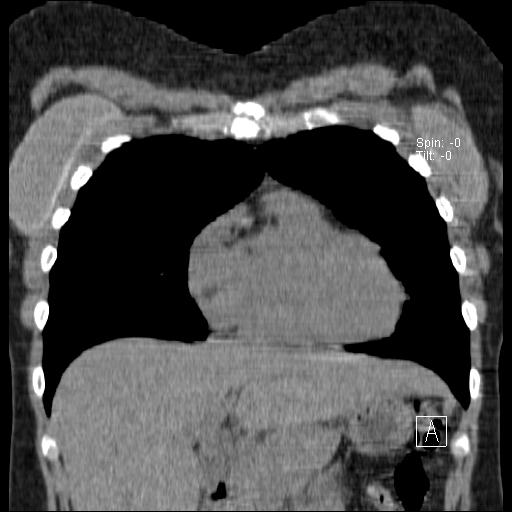

New CT images (without contrast) for 40 year old female with silicone breast implants. Formal diagnosis is expected soon. Images from 2010 can be seen here http://radiology-images.blogspot.com/p/40-year-old-female-silicone-implants.html

Please see also already added images in sagittal view Sagittal